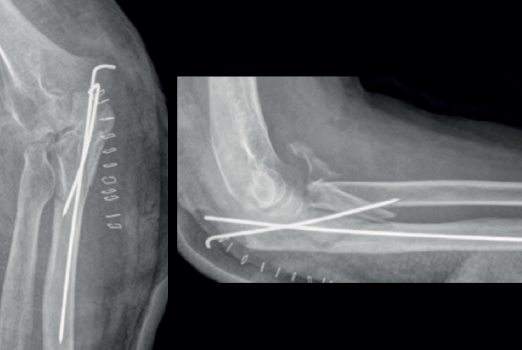

Las placas colocadas en la superficie posterior del cúbito son el sistema de fijación recomendado, proporcionando una fijación más resistente que los cerclajes con agujas de Kirschner y además permiten la fijación adicional de los fragmentos óseos y de la coronoides con tornillos o placas ortogonales en las superficies medial o lateral en los casos con gran conminución metafisaria(1,2,17). Las placas especialmente diseñadas de olécranon (Figuras 5 y 6) o las placas de compresión dinámica de contacto limitado (LC-DCP) de 3,5 mm conformadas para adaptarse a la morfología del cúbito son preferibles a las placas semitubulares, al aportar una fijación más estable(2,18,19).

Cuando la fractura del olécranon incluye una fractura de la coronoides, la reducción y la fijación de esta es condición imperativa para conseguir la estabilidad humerocubital (Figuras 7, 8 y 9). La reducción puede llevarse a cabo a través de la fractura del olécranon o por medio de un abordaje medial, separando o a través de la musculatura flexora/pronadora, teniendo identificados y protegidos el nervio cubital y el fascículo anterior del ligamento colateral medial. En los casos en los que es necesario realizar la sustitución de la cabeza del radio por una prótesis, también es posible el acceso lateral a la fractura de la coronoides. En general, el fragmento permite la fijación con tornillos desde posterior a anterior, a través de la placa posterior o independientes de esta, o en ocasiones desde anterior a posterior. La utilización de placas de 2,7 mm o específicas de coronoides, y técnicas de suturas no reabsorbibles atadas sobre el cúbito proximal o sobre la placa de fijación del cúbito son otras opciones(13,17). Para los grandes defectos óseos o fracturas irreconstruibles de la coronoides, se han descrito injertos óseos de la cresta ilíaca e injertos osteocondrales de la cabeza del radio con resultados impredecibles debido a la osificación heterotópica y a la reabsorción ósea del injerto(20,21).

Las fracturas complejas del cúbito que afectan al olécranon o a la coronoides pueden fijarse de “proximal a distal”(1) o de “distal a proximal”(22) en función de lo que resulte más fácil en cada caso. En la fijación de “proximal a distal”, el fragmento proximal del olécranon se fija temporalmente a la tróclea con una o varias agujas de Kirschner de 1,5 mm y el cúbito se reduce sobre el fragmento de olécranon proximal. La fijación de “distal a proximal” se centra inicialmente en la reducción y la fijación de los fragmentos distales del cúbito con objeto de simplificar los trazos de fractura y finalmente proceder a la reducción y la fijación con el fragmento proximal del olécranon. En la reconstrucción de la escotadura mayor del olécranon, se deben tener en cuenta la relación anatómica normal de la coronoides con el olécranon y la existencia de la zona desprovista de cartílago en la escotadura mayor. La incongruencia articular en las fracturas conminutas tiene menos impacto en el resultado clínico que la falta de alineación, altura y rotación de la escotadura mayor del olécranon(1).